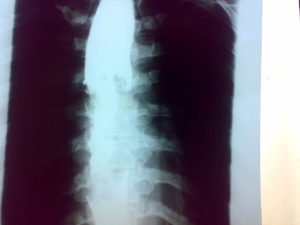

Esophageal cancer (or oesophageal cancer) is malignancy of the esophagus.Cancer of the esophagus, CT with contrast.

食道がんとは、食道の組織内に発生するがんの総称です。

日本人の食道がんは、約半数が胸の中の食道の真ん中から発生します。食道がんは食道の内面をおおっている粘膜の表面にある上皮から発生します。食道の上皮は扁平上皮でできているので、食道がんの90%以上が扁平上皮がんです。食道がんは全がんの4%前後を占めております。50歳代以降は加齢とともに急激に増加し、ピ-クは60歳代です。男女比は5:1で男性に多いがんです。経年的にみると男性では横ばいであるのに対し、女性では年々減少しております。胃がん、大腸がんを含む消化管のがんの中では予後は極めて悪いのが食道がんです。これはリンパ節転移が多いことと、食道は他の消化器臓器と異なり漿膜(外膜)を有していないため、比較的周囲に浸潤しやすいことが上げられます。